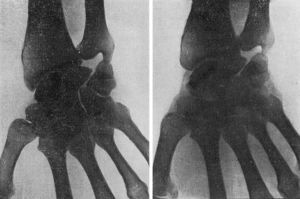

La extirpación de todo el escafoides o de un fragmento del mismo (Dwyer y Cave, Gurd, Hirsch, Dewey, Sashin, etc.) no ha dado buenos resultados provocando una grave alteración de la función de la muñeca (Vernon Luck, Kemper) (Fig. 1). Las perforaciones múltiples a lo Beck han sido realizadas con escasos resultados (Soto Hall, Bunnel, Obletz-Halbsteisn, etc.). Tampoco se ha conseguido solucionar al problema con la sustitución del escafoides por una prótesis acrílica, de vitallium, etc. (Waugh, Rauling).

El injerto de cortical, ya realizado por Adams y Leonard (1928), fue divulgado por Murray (1946) (Fig. 2). Este autor a través de una incisión posterolateral esqueletiza el borde externo del escafoides practicando a continuación un túnel que, partiendo de la tuberosidad, atraviesa ambos fragmentos. A lo largo de este túnel hace pasar un injerto de cortical que inmoviliza ambos fragmentos. Esta técnica es empleada no sólo en casos de seudoartrosis, sino también en fracturas recientes con magníficos resultados (95 por 100 de consolidaciones).

Mc. Laughlin divulga la técnica de ostesíntesis del escafoides con tornillo de vitallium, aplicada incluso en las fracturas recientes, con la cual obtiene magníficos resultados (Fig. 3). En ninguno de los casos de seudoartrosis tratados con esta técnica llega a obtener una consolidación radiológica, pero los resultados funcionales son buenos en todos ellos debido a la perfecta inmovilización de los fragmentos. Passer (1960) expone las ventajas que ofrece la ostesíntesis con tornillo en las seudoartrosis del escafoides, obteniendo resultados funcionales en 18 casos de los 20 en que ha realizado esta técnica.

La resección de la estiloides del radio (Bernard and Stubbins, Smith-Friedmann, 1956, etc.) ha sido propuesta con la finalidad de evitar la acción microtraumatizante que produce dicha apófisis sobre el fragmento distal del escafoides. Esta técnica ha sido realizada aisladamente, pero, en general, se asocia a un medio de síntesis. Rusee modifica la técnica de Matti asociando al injerto de esponjosa un injerto de cortical con el cual asegura la inmovilización. Merle D’Aubigné (1958), por último, propone la ostesíntesis con tornillo combinada con un injerto de cortical (Fig. 4).